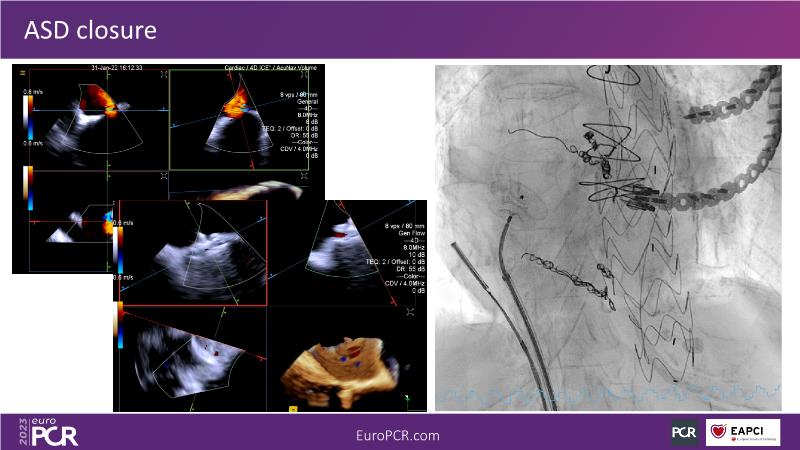

Use of 4D ICE in tricuspid and mitral valve interventions

Watch this session to know the challenges of TV imaging, to get an overview on 4D ICE technology, and to study both a transcatheter tricuspid valve procedure and a transcatheter mitral valve procedure through different case presentations, that will then be discussed.

- To get familiar with the 4D ICE technology and how it can support the imaging and guidance in complex structural heart disease interventions

- To understand the use of 4D ICE and benefits in tricuspid and mitral valve interventions